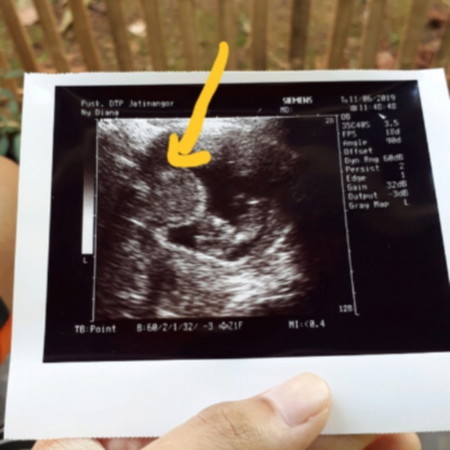

Hai bunda ini usg waktu hamil 11 minggu aku penasaran itu yang aku tandai apa ya bun?

Kalau bayinya yg sebelahnya bun